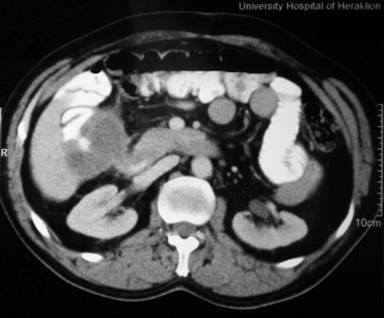

A 53-year-old man with a history of adenocarcinoma of the right lung presented with gastrointestinal bleeding. Adenocarcinoma of the lung was diagnosed six months prior to he gastrointestinal bleeding and was treated with a right pneumonectomy. Histological examination demonstrated a median to low differentiation papillary adenocarcinoma infiltrating the pleura. Gastroscopy showed a bleeding duodenal mass, and a contrast-enhanced CT scan of the abdomen revealed a tumor of the pancreatic head measuring 5x3x3 cm (Figure 2). Failure of conservative measures led to a pancreaticoduodenectomy. Metastatic lesions were also found during the laparotomy and were excised with a segmental enterectomy. Histological examination of the surgical specimen demonstrated metastatic adenocarcinoma of the lung. On the 12th postoperative day, the patient presented with intra-abdominal bleeding and was reoperated on; hemorrhage from the pancreatic bed was controlled by a tamponade. The patient recovered from the second hemorrhage but succumbed to new massive gastrointestinal bleeding on the 30th postoperative day.

Figure 1. Solitary metastatic lesion to the head of pancreas from lung cancer as imaged by contrast-enhanced CT scan (Case #2). |